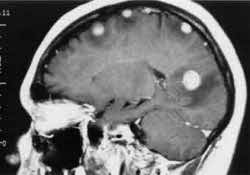

Классических форм эпилептиформной активности не выявлено. Регистрируются единичные диффузные острые волны альфа-,бета- диапазона. Лёгкие ирриативные изменения без чёткой локализации. Возможна лёгкая дисфункция срединных структур.Когда случился после операции первый приступ сделали МРТ рецидива не обнаружено, но есть рубцово-атрофические изменения головного мозга. Как нам остановить эти приступы и из-за чего они образуются если убрали опухоль,которая их давала?Помогите пожалуйста подобрать схему лечения. Может стоит принимать не "Финлепсин"ретард, а таблетки простые или увеличить дозировку?Заранее благодарна

Помогите, пожалуйста расшифровать результаты анализов. Сразу оговорю, что на анализы направили, из-за частых головокружений, которые в последнее время привели даже к двум приступам с судорогами... Была сделана компьютерная томография головного мозга, в результате которой обнаружен небольшой очаг в правой височной доле... Но нейрохирург ничего страшного не увидел в снимках и направил сдать кровь на инфекции...